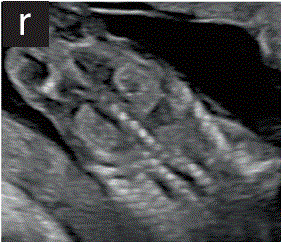

7.1.2 胎儿肾脏通常在其预期的脊柱旁位置可见为豆形,轻微回声结构,典型的肾盂中央低回声(图2r)。

胎儿mt是什么检查什么疼吗【文献学习/规范指南】ISUOG实践指南(2023更新): 11-14周胎儿超声检查(全文)_https://www.jmylbn.com_新闻资讯_第21张

(r)胎儿胸腹部冠状面图,双侧胎儿肾脏(轻微回声)、胸椎和脊柱和骨盆骨

图2 11+0至14+0周时,可作为详细胎儿超声检查的一部分获得的解剖图。